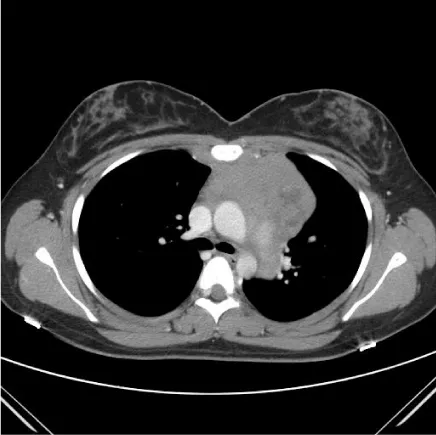

Case 1 is a 26 year old pregnant female who initially presented in January 2012 at 25 weeks gestation with left shoulder pain. A routine work up performed by her obstetrician revealed a WBC count of 200,000 with 92% circulating blasts (Figure 1). She was referred to the high risk obstetrics service at this hospital and hematology was consulted for management. Peripheral blood flow cytometry was performed which was consistent with γδ T-ALL. She underwent induced vaginal delivery which was uncomplicated and was then transferred to the hematology inpatient service for treatment. Following transfer, a bone marrow aspiration and biopsy was performed that confirmed acute lymphoblastic leukemia, T-cell lineage, gamma delta subtype (Figure 2). The blasts expressed CD3, CD5 and TdT by immunohistochemistry. Flow cytometry showed that the blasts expressed CD3, gamma/delta TCR, CD2, CD5, CD10 and CD45. CT of the chest, abdomen and pelvis was performed which showed a large anterior mediastinal soft tissue mass and hepatosplenomegaly (Figure 3).